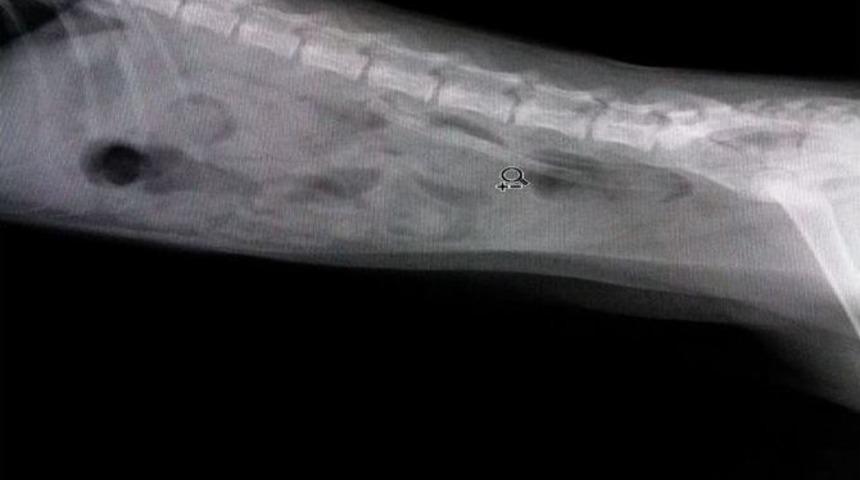

Muğla’nın Marmaris ilçesinde oyun oynadığı 22 cm uzunluğundaki serum hortumunu midesine indiren yavru kedi veteriner kliniğinde gerçekleştirilen ameliyatla kurtarıldı.Edinilen bilgiye göre, Bir vatandaşa ait üç aylık yavru kedi, bahçede 22 santimetre uzunluğundaki serum hortumu ile oynadığı sırada hortumu yutarak midesine indirdi. Yavru kedi 3 gün boyunca bağırsaklarına yerleşen hortumla dolaştı. Küçük kedinin durgun halinden şüphelenen sahibi veteriner kliniğine götürdü. Röntgeni çekilen hayvanın bağırsaklarına yerleştiği tespit edilen hortum başarılı bir ameliyatla makatından çıkartıldı.Marmaris Villapet Veteriner Kliniği Hekimi Behçet Düzgün yaptığı açıklamada, "Yavru kedi bize geldiğinde karın bölgesinde sertlik vardı. Röntgende hayvanın bağırsağına yerleşmiş halde serum hortumu tespit ettik ve operasyona karar verdik. Kısa bir müdahale ile makat bölümünden 22 cm uzunluğundaki hortumu çıkartmayı başardık. Şanslı bir kediymiş ki hortumun uç kısmı mide ya da bağırsaklarda herhangi bir zarara neden olmamış” dedi.